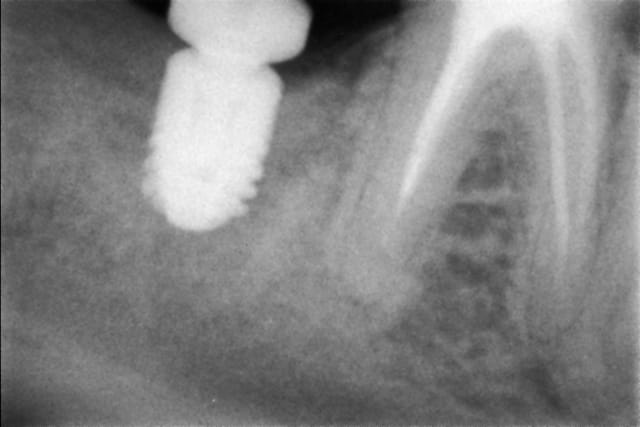

Echec n°5

Implantation différée de 2 mois dans un site 47.

Rien à signaler sur ce cas, j'ai toujours pas compris ce qui s'est passé, mais j'ai diagnostiqué la fibrointégration ce lundi. Dépité, pas compris...

Ah si ! c'est la faute à Tekka !

C'est vrai que ça soulage...